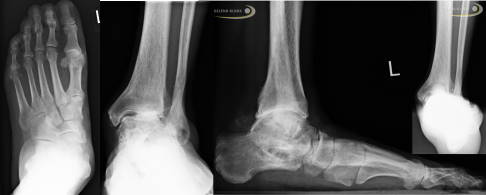

Neben der klinischen Untersuchung des Sprunggelenks und einer umfassenden Einschätzung und Lokalisierung der Schmerzen liefern bildgebende Verfahren wie Röntgen und MRT (Magnetresonanztomographie) dem Arzt wichtige Hinweise auf ein mögliches Impingement im Sprunggelenk.

Jede Untersuchung beginnt mit einer Röntgenaufnahme in verschiedenen Ebenen. Das ist meistens ausreichend, um eine eindeutige Diagnose zu stellen. Alle knöchernen Ursachen des Sprunggelenk-Impingements, vor allem Osteophyten an den Gelenkflächen, Exostosen und alle Varianten des hinteren Fortsatzes des Talus (Processus trigonum) bis hin zu Frakturen, macht das Röntgenbild sichtbar.

Das Röntgenbild in mehreren Ebenen zeigt knöcherne Veränderungen des Sprunggelenks, die typisch für ein Impingement sind. © Gelenk-Klinik